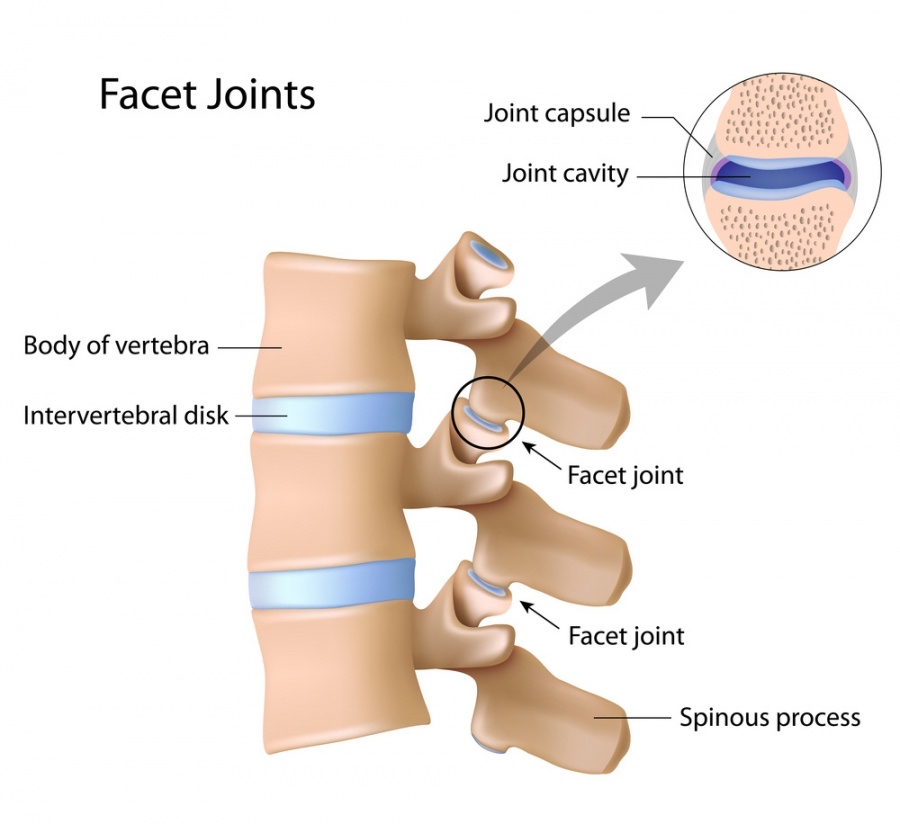

- Facet Block Injections

- Rhizotomy